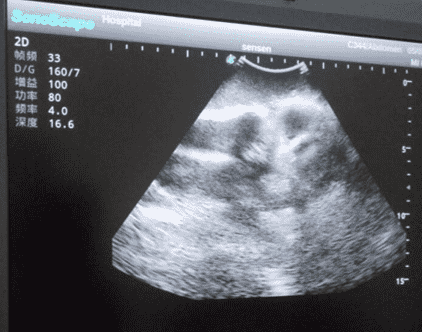

2)   Real clinical ultrasound images with clear anatomical structures like femur, joint cavity, etc.

3)   Compatible with various real ultrasound machines